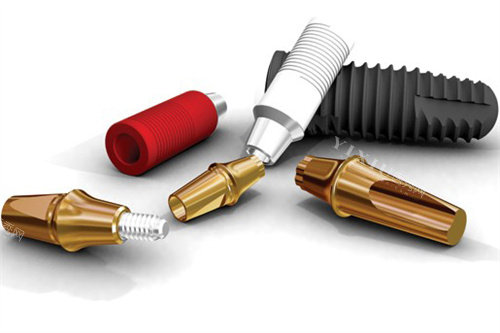

三、价格差异核心因素:3大变量决定比较终费用

植体品牌与技术

材料成本:四级纯钛(国产/韩国) vs 五级钛合金(美国) vs 锆钛合金(瑞士)

表面处理:SLA(大颗粒喷砂) vs SLActive(亲水处理,骨结合快30%)